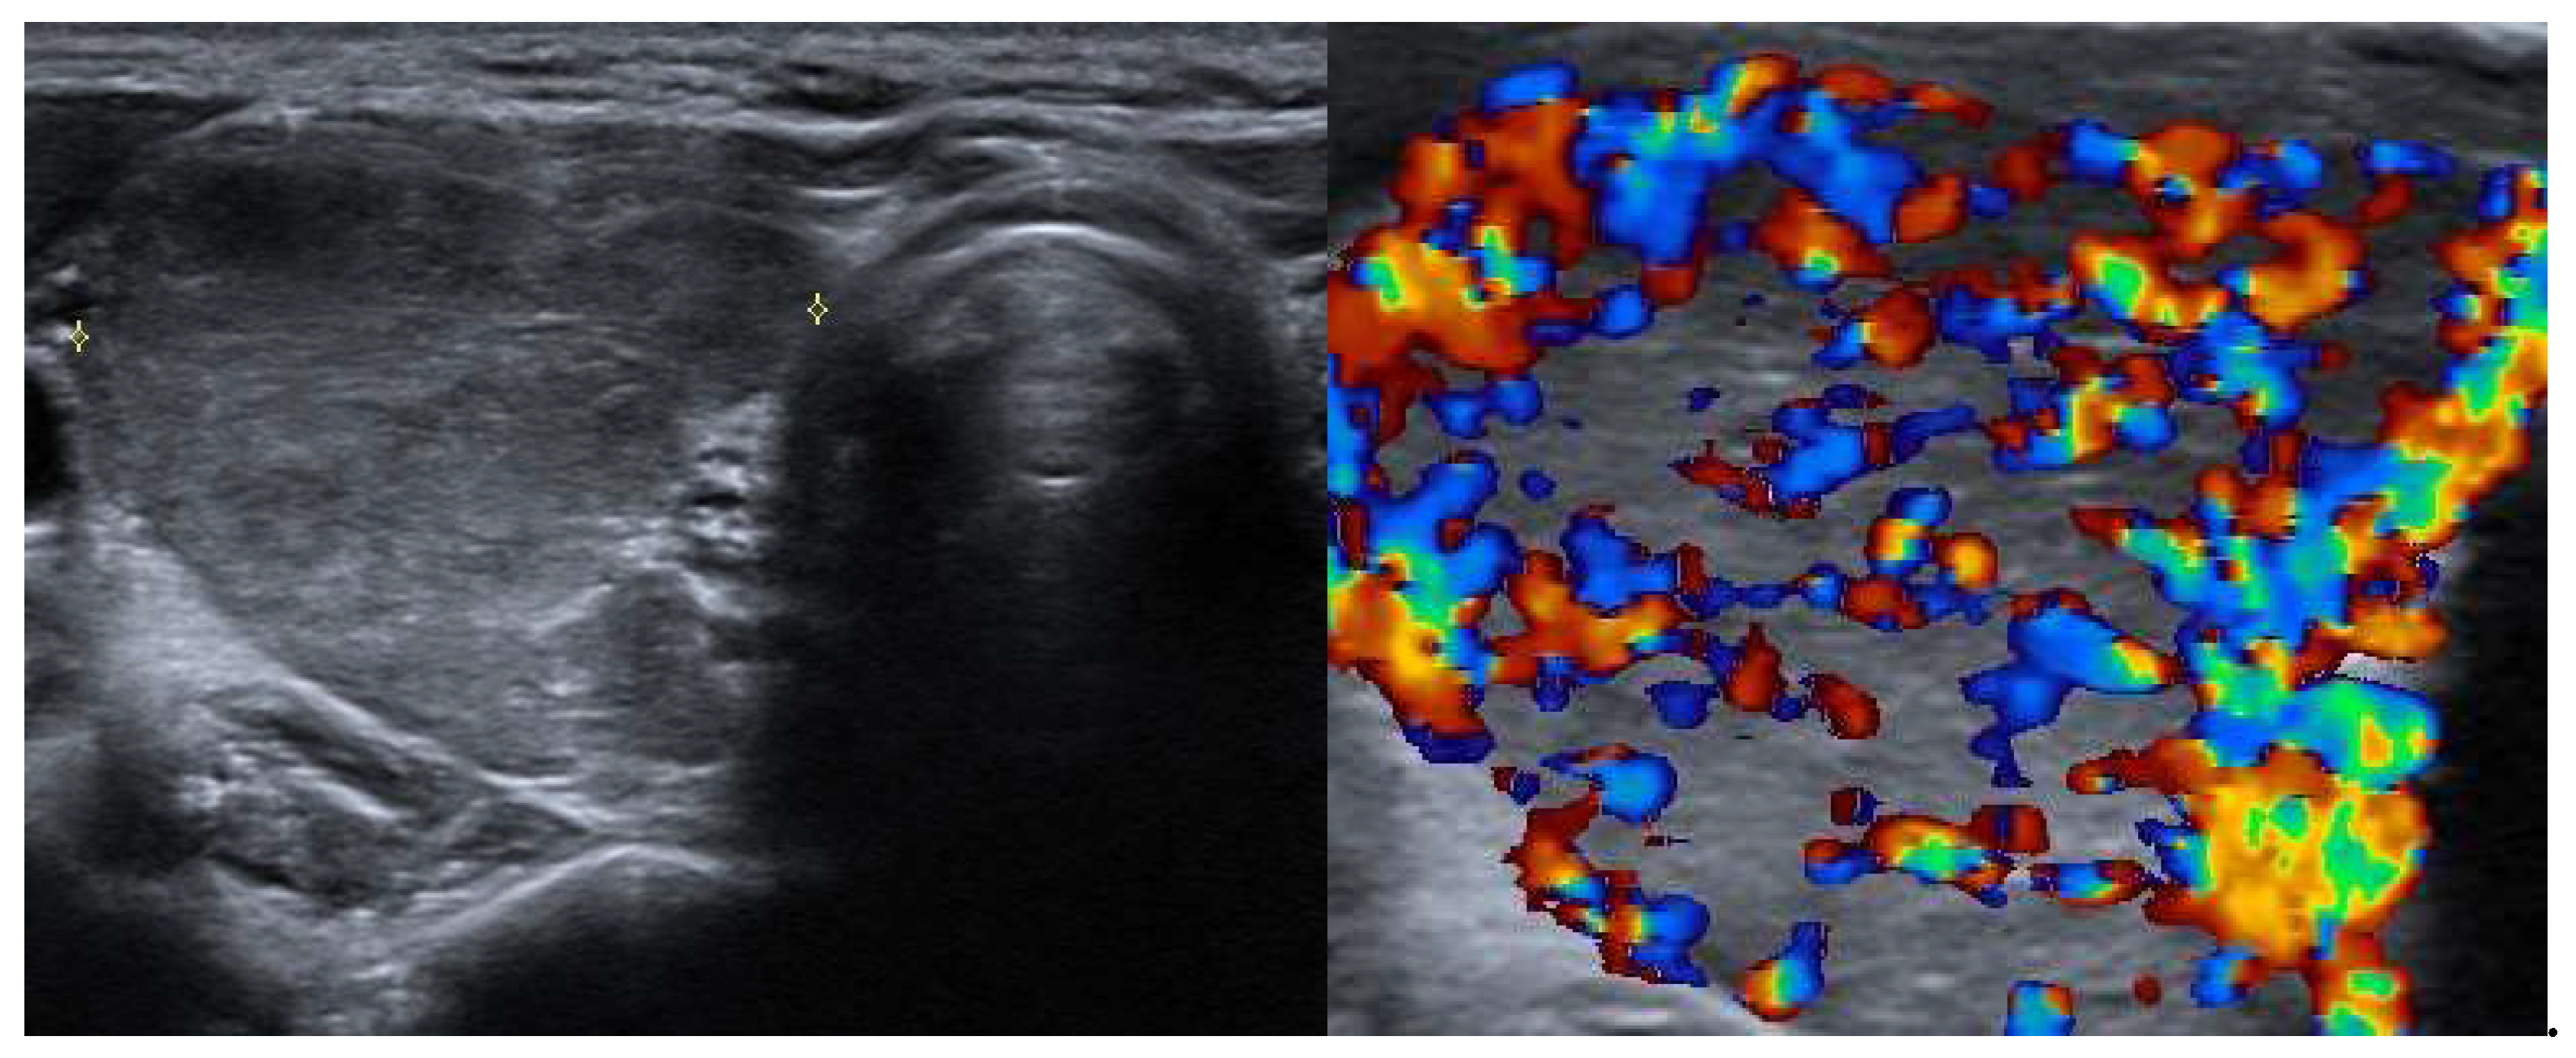

3.2.4. Destructive Thyroiditis

- Enlarged gland: the thyroid may appear enlarged but with a texture distinct from that seen in Graves’ disease or toxic multinodular goiter. Pseudonodules may be present.

- Hypoechoic and heterogeneous texture: the thyroid tissue may display a hypoechoic and heterogeneous pattern due to inflammation and necrosis, particularly in subacute thyroiditis (Figure 2).

- Reduced vascularity: unlike Graves’ disease, thyroiditis often shows diminished or absent vascularity on Doppler ultrasound due to reduced blood flow in the inflamed tissue.